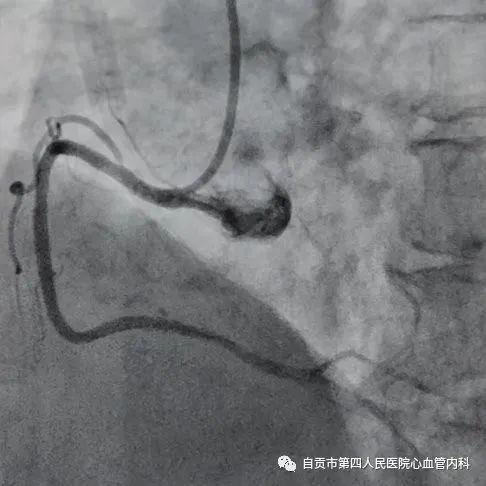

作者:汤勇 自贡市第四人民医院心血管内科引进又一利器“冠脉内超声检查(IVUS)”,助力冠心病精准治疗,目前我国冠心病发病率呈现一个高发的态势,冠心病的发病年龄也呈年轻化的趋势,20-30岁的人群发生急性心肌梗死也不少见。 ![]() 冠脉完全闭塞导致心梗 ![]() 急诊手术成功开通血管 药物加冠脉支架治疗是治疗冠心病的常规治疗手段,我们通常选择冠脉造影对患者的冠状动脉血管检查,由于冠脉造影显示的血管图像是二维图像,并不能完全真实地反映患者冠脉病变的实际情况,有可能造成不必要的支架植入,判断支架的大小完全依赖经验与造影图像,也有可能造成支架大小,长度选择不当。 ![]() ![]() 为了更精准对冠心病患者治疗,优化支架植入,减少支架植入的并发症的发生。 ![]() IVUS图像 ![]() 造影显示需要支架治疗 我院引进了美国波科公司的冠脉内超声检查(IVUS)检查设备,对患者的冠状动脉进行实时检查,为临床医生在对冠心病患者是否需要支架治疗,支架合理应用提供更为准确得信息。 ![]() 我们有一位患者在西昌某院因心肌梗死,行右冠状动脉支架治疗,当时冠脉造影检查提示右冠状动脉支架有一重度狭窄,建议择期再行支架治疗,患者慕名来我院来进一步检查。从冠脉造影的情况确实需要进行支架治疗,由于患者年轻,已安置支架4枚,故决定对患者进行冠脉内超声检查(IVUS)检查。 ![]() 支架局部膨胀不全 ![]() 冠脉内超声检查(IVUS) ![]() 支架直径恢复正常 患者冠脉内超声结果提示管腔面积能够满足心肌血供,且病变邻近血管直径大于5mm,不适合支架治疗。故建议其药物治疗,必要时复查造影。另外该患者造影显示已安置的支架显示膨胀不全的可能,进行冠脉内超声检查后显示支架内有明显膨胀不全的征象,故予以球囊扩张,支架管腔直径恢复正常。 在今后的冠心病治疗上,冠脉超声检查将发挥更大的作用,特别是复杂病变,左主干病变,钙化病变,闭塞病变方面,将大大减少冠脉介入治疗的并发症,再次支架治疗的发生率降低,将大大提高我院冠心病的精准治疗水平。 ![]() ![]() |